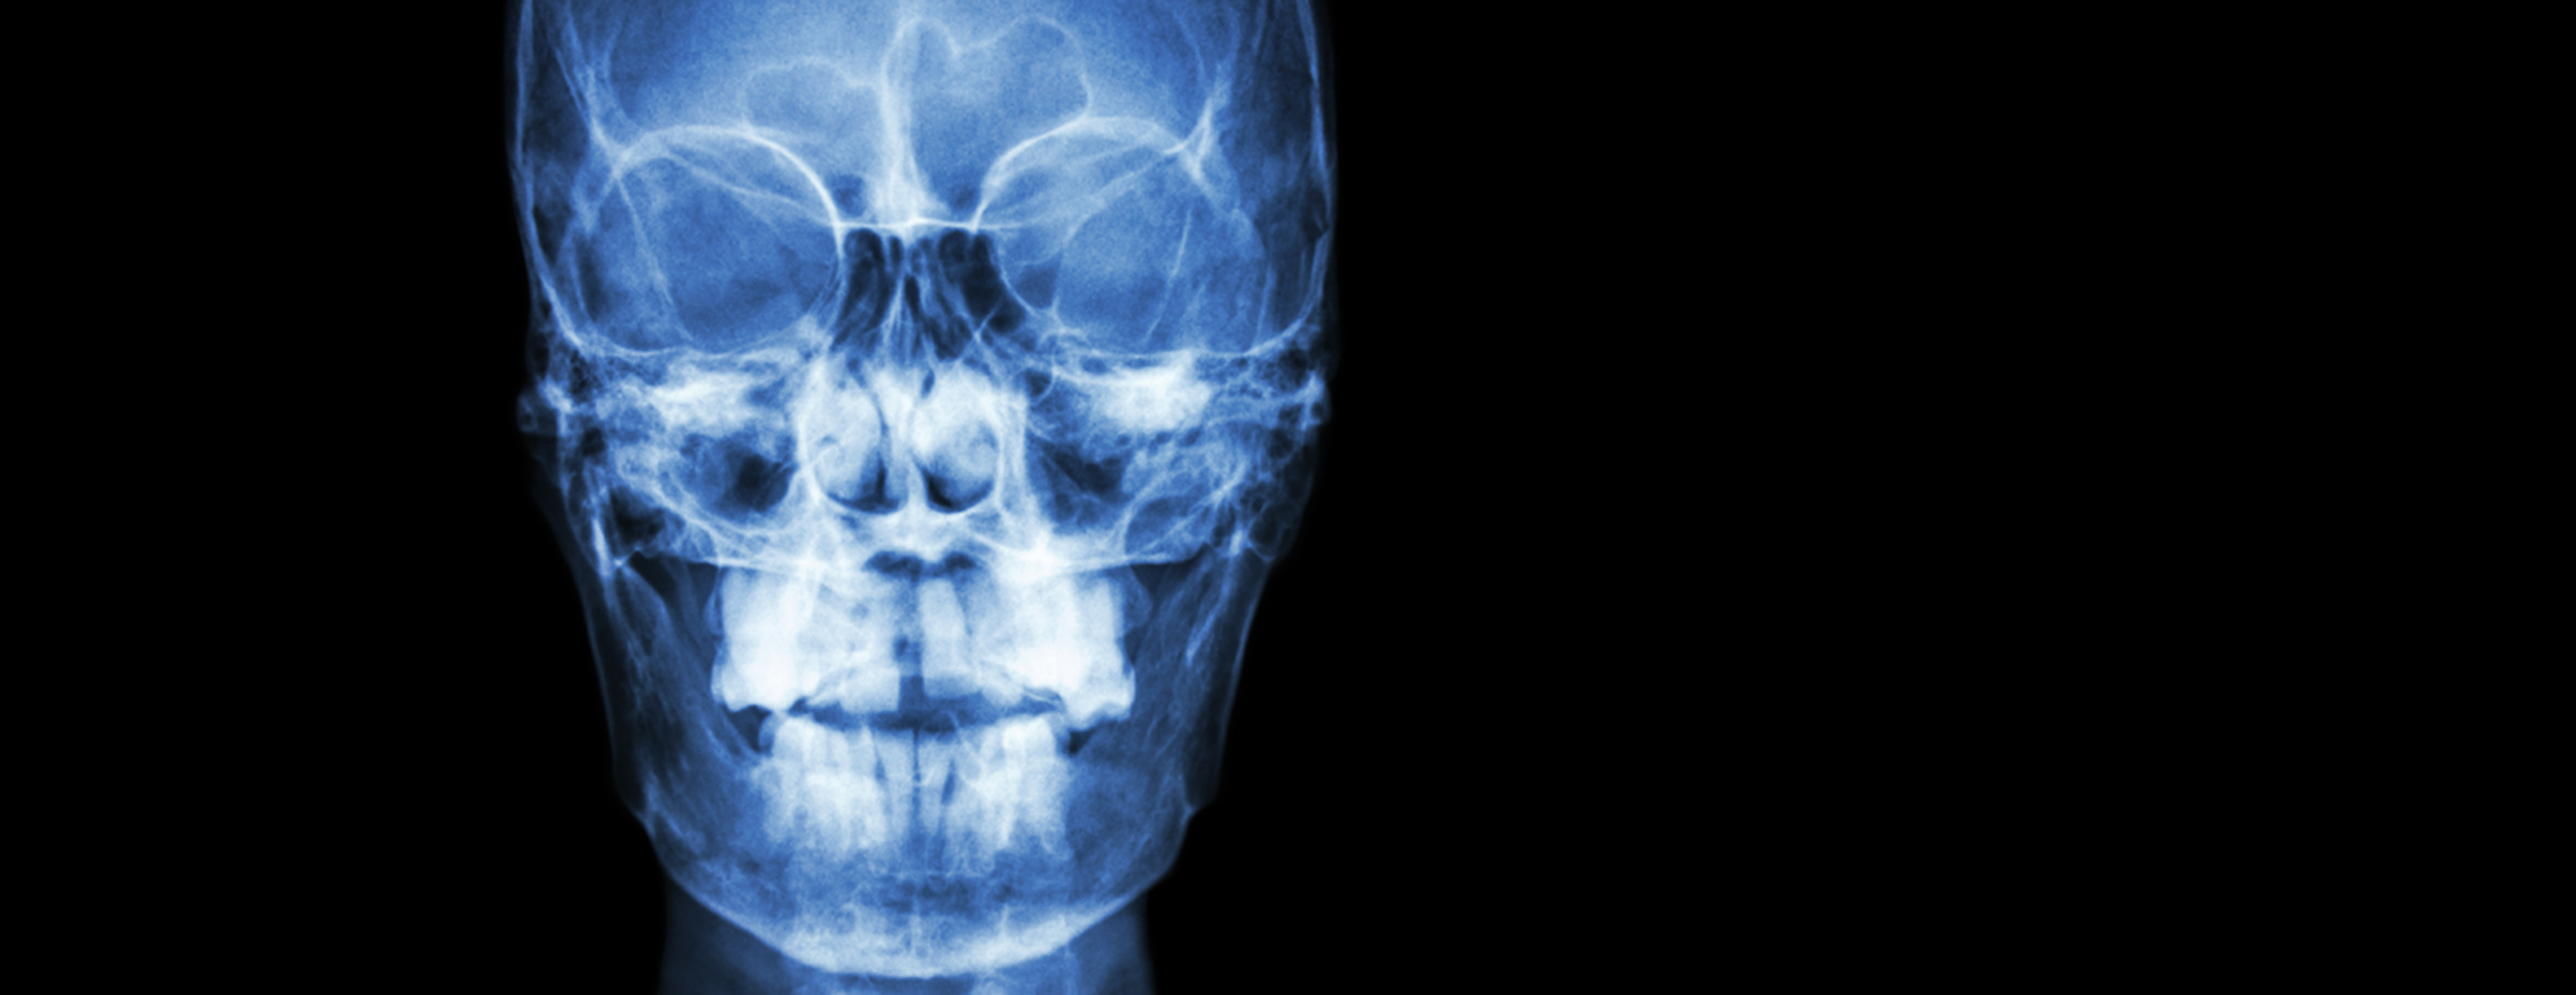

Sinus x-ray

A sinus x-ray is taken in a hospital radiology department. Or the x-ray may be taken in your health care provider's office. You will be asked to sit in a chair so that any fluid in the sinuses can be seen in the x-ray images. The technologist may place your head in different positions as the images are taken.

The sinuses are located behind the forehead, nasal bones, cheeks, and eyes. When the sinus openings become blocked or too much mucus builds up, bacteria and other germs can grow. This can lead to an infection and inflammation of the sinuses called

The x-ray may detect an infection, blockages, bleeding or tumors.